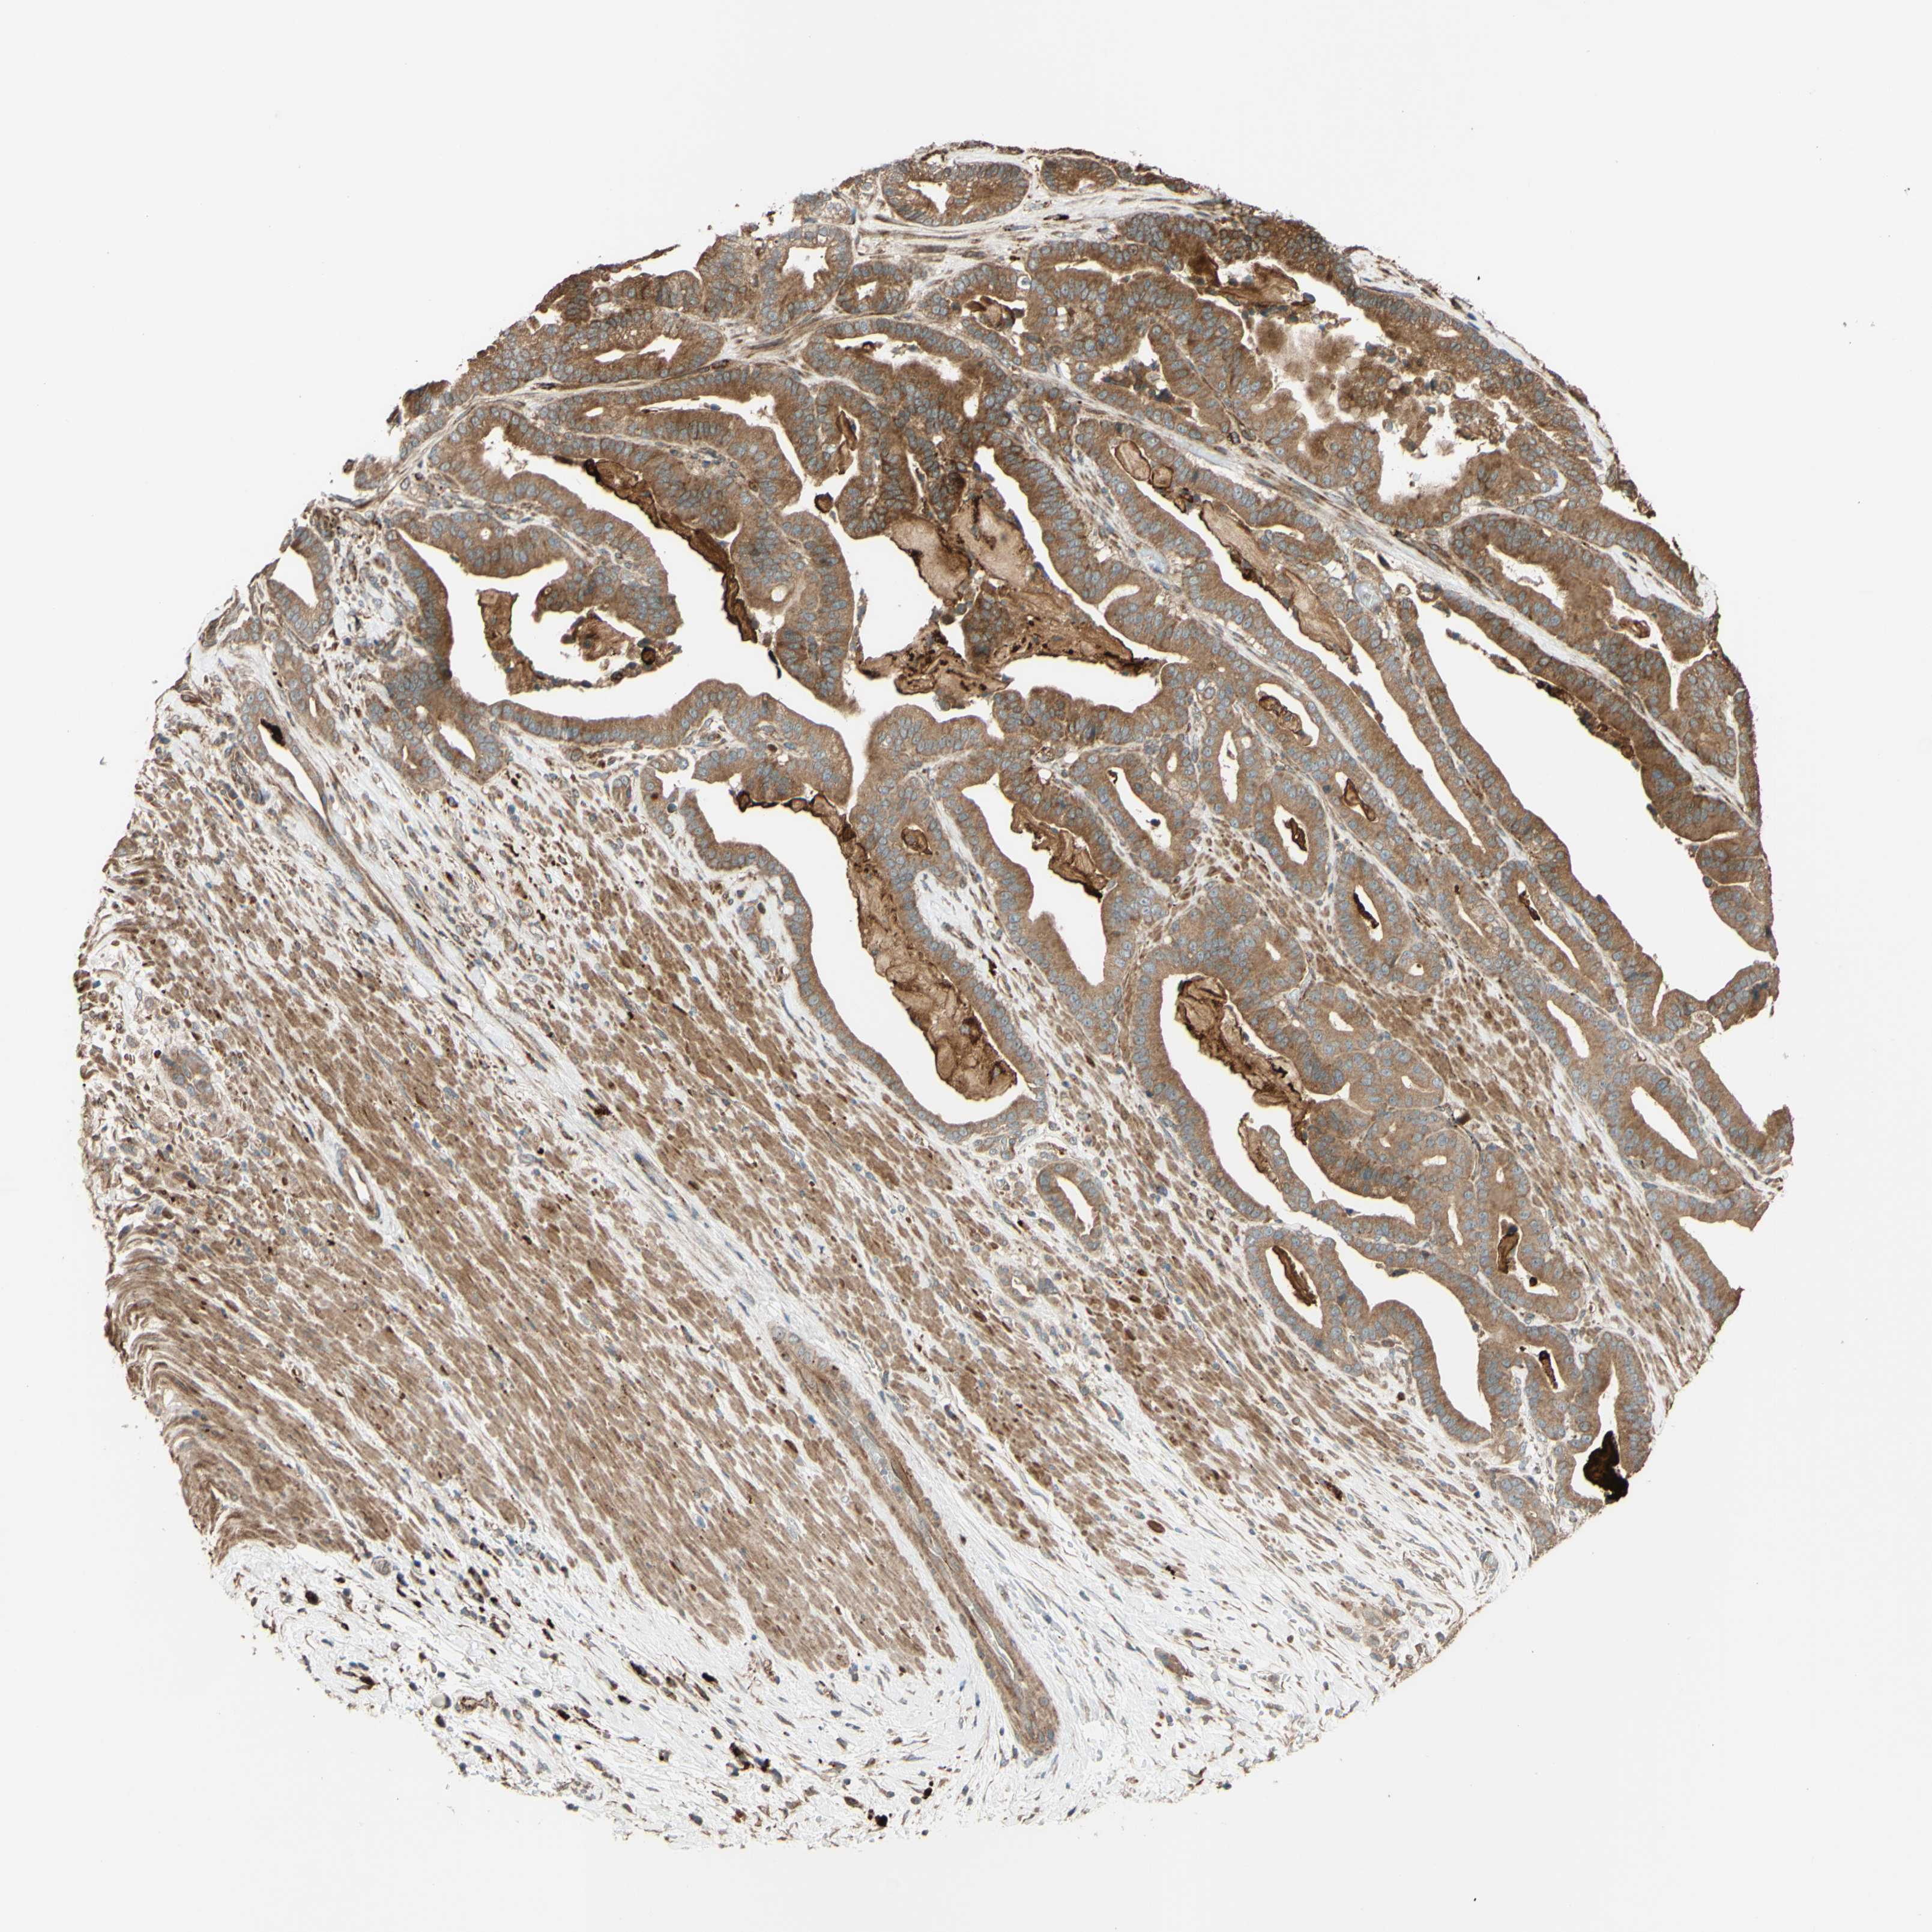

PANCREATIC CANCER - Protein expressioni

A mouse-over function shows sample information and annotation data. Click on an image to view it in a full screen mode. Samples can be filtered based on level of antibody staining by selecting one or several of the following categories: high, medium, low and not detected. The assay and annotation is described here.

Note that samples used for immunohistochemistry by the Human Protein Atlas do not correspond to samples in the TCGA dataset.

Antibody stainingi

Antibody staining in the annotated cell types in the current human tissue is reported as not detected, low, medium, or high, based on conventional immunohistochemistry profiling in selected tissues. This score is based on the combination of the staining intensity and fraction of stained cells.

Each image is clickable and will lead to virtual microscopy that enables deeper exploration of all samples and also displays staining intensity scores, fraction scores and subcellular localization as well as patient and tissue information for each sample.

Antibody HPA023652

Antibody CAB011455

Staining

High

Medium

Low

Not detected

Intensity

Strong

Moderate

Weak

Negative

Quantity

>75%

75%-25%

<25%

None

Location

Nuclear

Cytoplasmic/membranous

Cytoplasmic/membranous,nuclear

Adenocarcinoma, NOS

Adenocarcinoma, metastatic, NOS